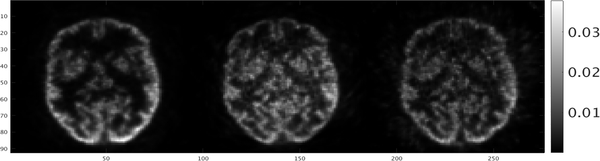

Slices of reconstructed volumes of mini-hot-rod and Hoffman brain phantoms are shown in Figs. 9 and 10. The 3.2 mm-diameter rods are clearly resolved. Incorporation of time-of-flight information in the image reconstruction process improved, slightly, the ability to resolve the smaller rods. Images of the Hoffman brain phantom also demonstrated improvement in the ability to resolve small structures due to the addition of TOF information..

Fig. 9.

Single slices through a Derenzo resolution phantom. Images were reconstructed with no TOF (left), with 280 ps (center) and 460 ps (right) kernels.

Single slices through Hoffman brain phantom. Images were reconstructed with no TOF (left) kernel, with 280 ps (center) and 460 ps (right) kernels.

Applying TOF for a small-diameter scanner, such as the one described in this work, will have only modest effect. This phenomenon is demonstrated by the moderate improvement to identification of small structures in images of the mini-hot rod phantom (Fig 9.) and Hoffman brain phantom (Fig. 10). Improvement was also hindered by the relatively poor system timing resolution (460 ps) (Fig. 8). Efforts to improve this phenomenon, likely due to time jitter introduced by attaching multiple modules, are currently under investigation.